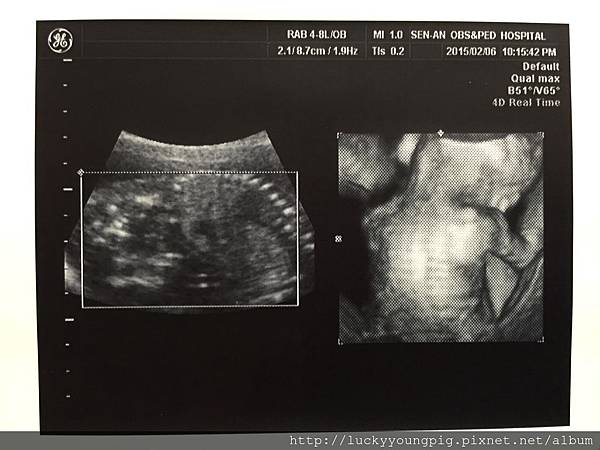

進了診間 醫生請我先照超音波 哇~太吸晴了

是4D的耶 這真的是滿足媽媽的眼慾 哈哈哈~

醫生照的非常仔細 也粉久

寶貝19w2d 頭圍腹圍大小正常 約300g哦~

醫生說 寶貝正在拉耳朵啦 哈哈哈~很調皮哦

醫生說 寶貝沒臍帶繞圍哦